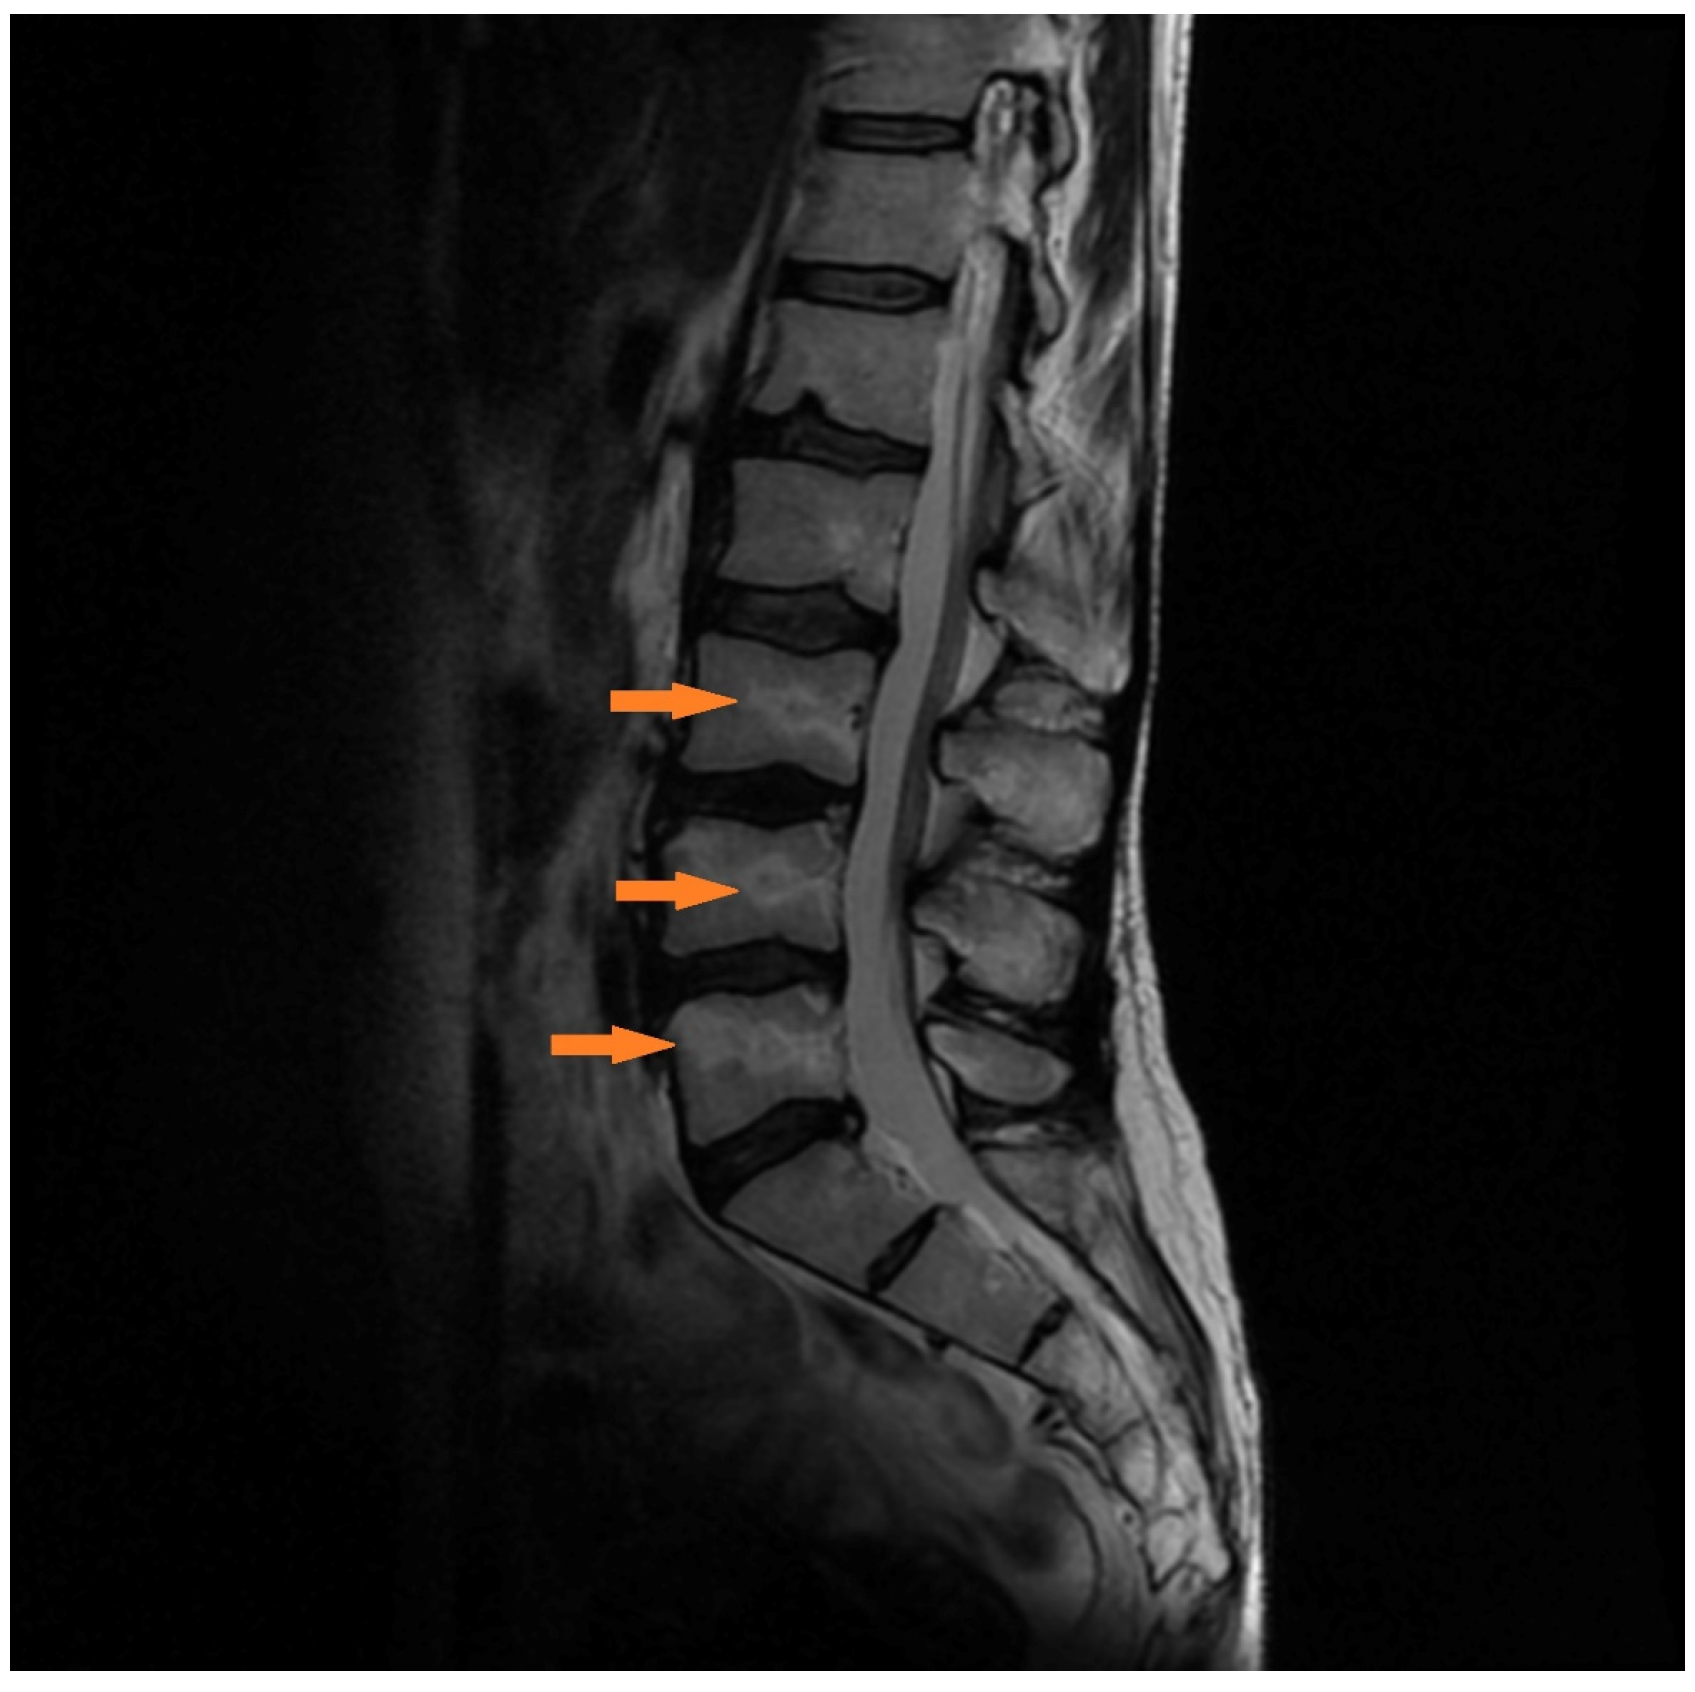

3.1.3. Case 3 (Patient No. 7)

4. Discussion